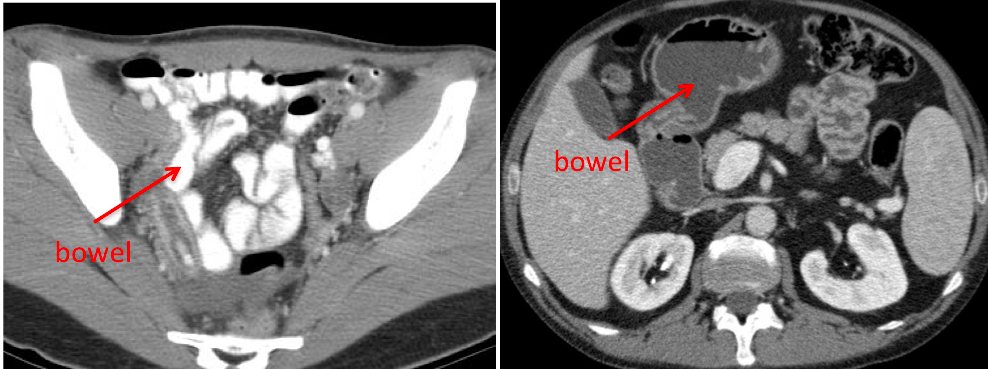

What are the indications for obtaining a CT?

How is it obtained? What contrasts are employed?

Abdominal pain, Bowel pathology, Tumors, Weight loss, vague symptoms

Positive (high density) oral contrast – differentiate between fluid collections (ie abscess) from bowel.

Negative (low density) oral Contrast (H: evaluate bowel mucosa and wall better

Timing of scan depends on the organ of interest and the pathology (hypervascular vs hypovascular), but involves some sort of scan delay (time from contrast injection to starting the scan).